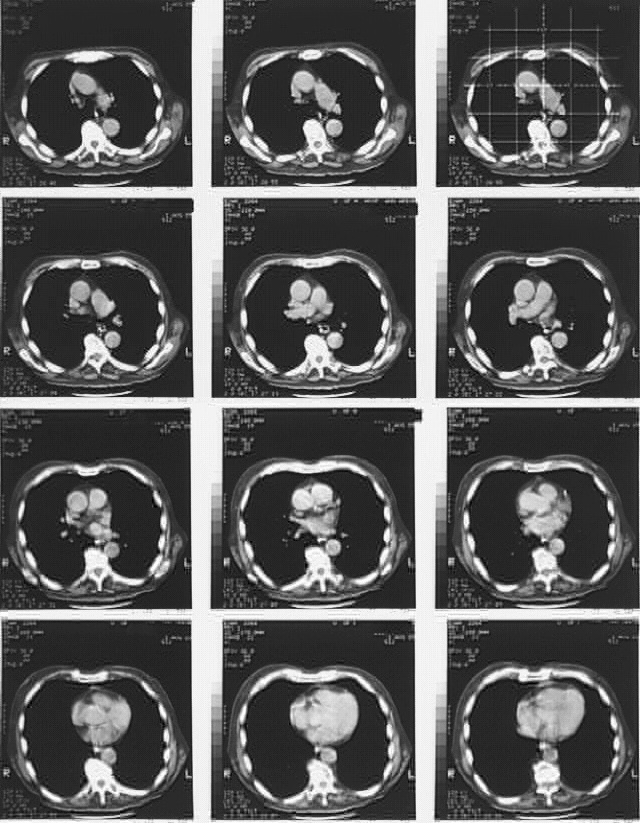

Radiology Images

Thorax-Chest CT Aug 2